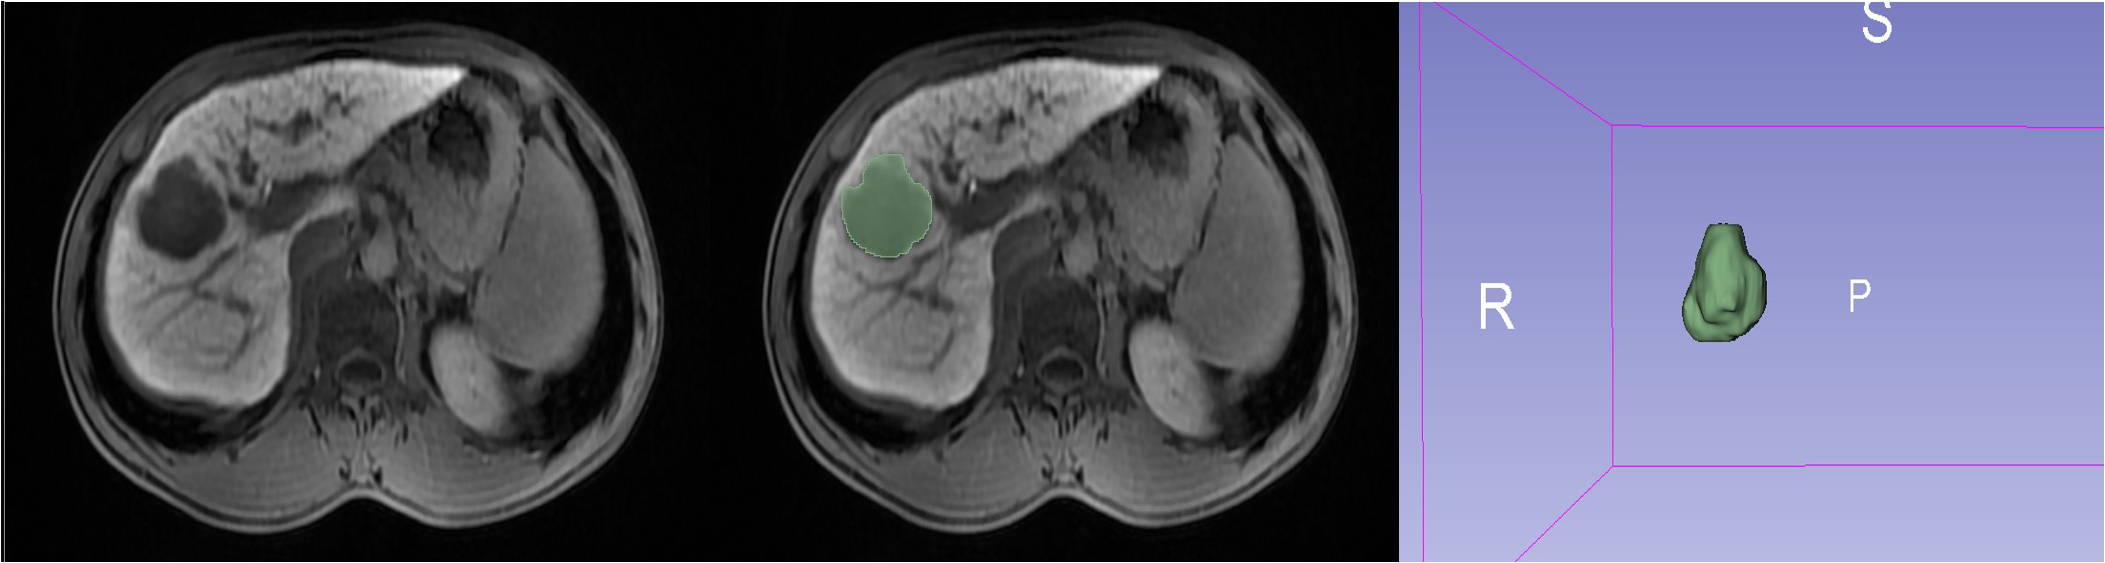

Figure 2

A representative ROI outlined in a 20 min HBP image using 3D Slicer software.

Using an imaging segmentation online software (3D Slicer, version 5.0.3), the ROI was determined by a radiologist with 5 years of abdominal diagnostic experience using the “segment editor” module to manually outline the ROI layer by layer during the HBP, which was later verified and validated by another senior radiologist. If the second radiologist questioned the segmented ROI of the first radiologist, a consensus was reached or the senior radiologist modified it accordingly. After one week, all 137 lesions were outlined again to assess the stability and reproducibility (Figure 2). Radiomics profiling was conducted using Python (version 3.9.15) and Pyradiomics (version 3.6.13), after the images were normalized and resampled (1,1,1), resulting in 9 image types (original, wavelet, square, squareroot, logarithm, exponential, gradient, localbinarypattern2D, localbinarypattern3D) and 7 feature classes [shape, first-order statistics, gray-level co-occurrence matrix (glcm), gray-level run length matrix (glrlm), gray-level size zone matrix (glszm), gray-level dependence matrix (gldm), and neighborhood gray-tone difference matrix (ngtdm)].